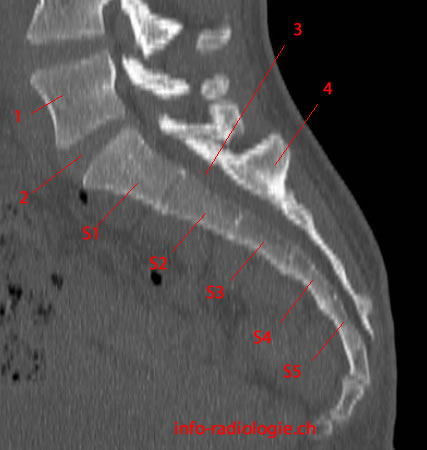

Рентгеновские снимки крестцово-копчикового отдела позвоночника